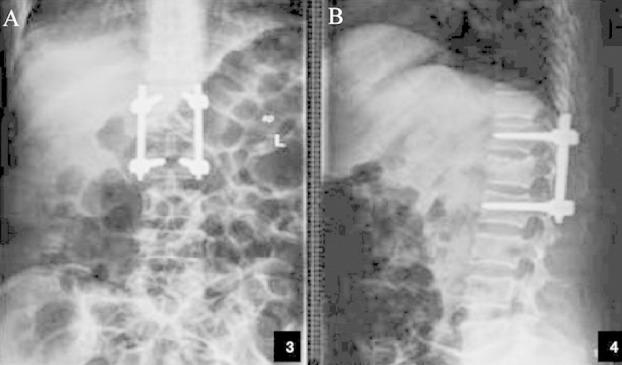

A total of 120 patients with TSF and SNI were selected and divided into a treatment group and a control group that were then treated by anterior decompression and posterior decompression respectively. The preoperative and postoperative motor scores, tactile scores, heights of injured vertebral body and Cobb's angles, as well as surgical times and intraoperative blood losses were recorded and compared.

Before surgeries, the motor score, tactile score, height of injured vertebral body and Cobb's angle of the treatment group were similar to those of the control group (P>0.05). After surgeries, the values of the treatment group were significantly different from those of the control group (P<0.05). The two groups also had significantly different intraoperative blood losses and surgical times (P<0.05).

Compared with posterior decompression, anterior decompression improved spinal cord function better and relived spinal cord compression more effectively with a more reasonable mechanics of internal fixation. Although this protocol caused more blood loss, the overall therapeutic effects were more satisfactory.